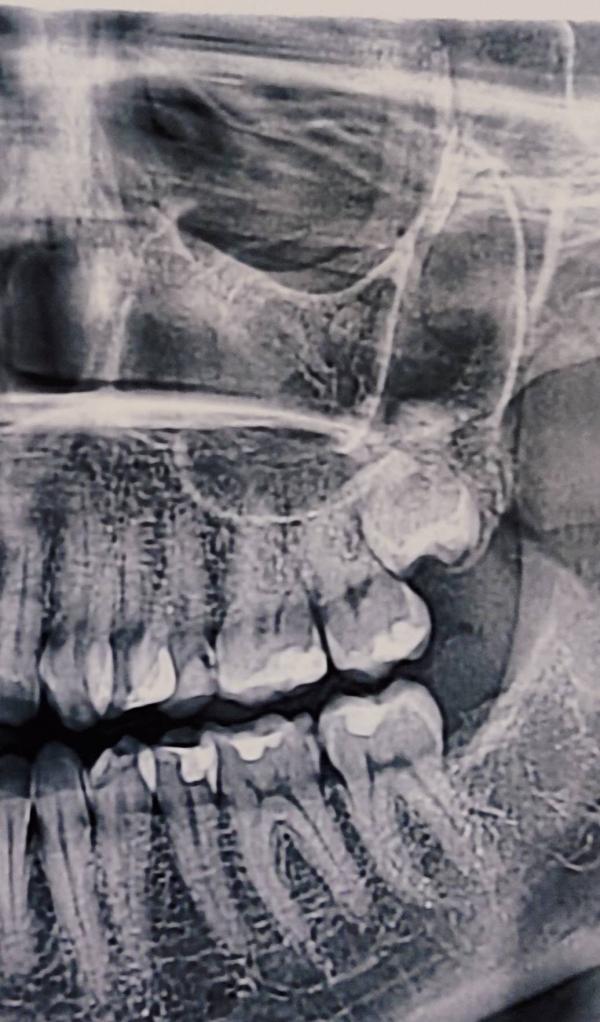

Зуб мудрости стоит в десне , не торчит даже..

Сегодня пришла к врачу на удаление, он отказался браться, сказал не сможет,надо удалять кость...

Сказали что ещё кость надо ломать бур машиной ... Зуб не прощупывается через десну(

@anna_karamelka мешают что давят на зубы и они становятся кривыми( остальные зубы мудрости так же были в десне,но росли горизонтально прям на корни других зубов

Да, мешают что давят на зубы и они становятся кривыми( остальные зубы мудрости так же были в десне,но росли горизонтально прям на корни других зубов